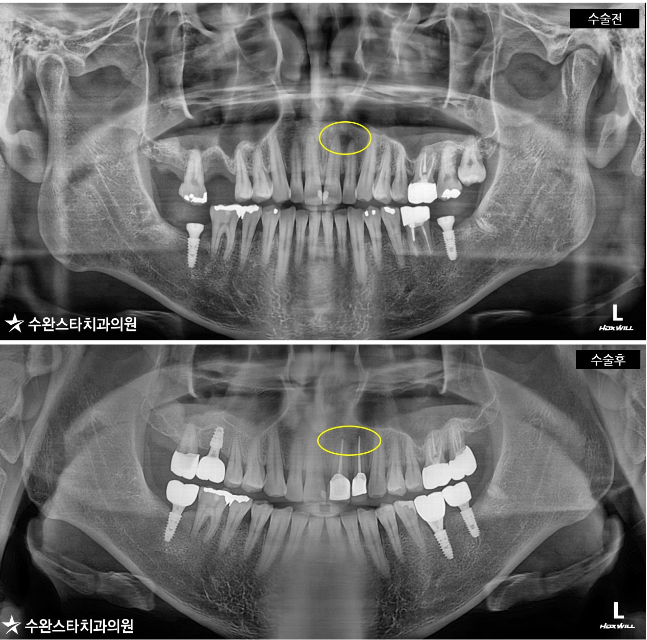

수술 전 파노라마, 30대 남성 (2019/8월 촬영)

표시된 까만 부분이

바로 염증으로 뼈가 녹은 부분인데

해당 부위는 신경과 혈관이

많이 분포한 부위입니다.

파노라마 전후 비교, 30대 남성 (2019/8월 ~ 2020/8월 촬영)

수술 후 1년 정도 경과 후 비교를 해보니 깨끗해졌네요.